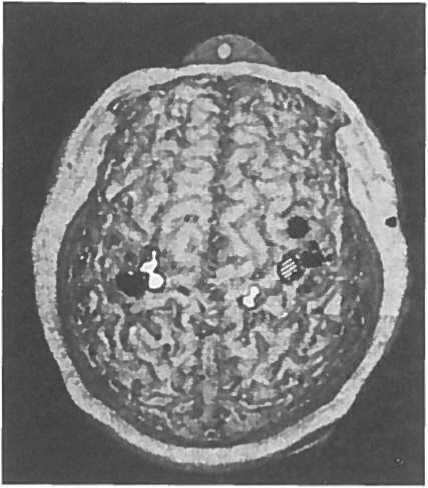

Независимо от того, какая из этих двух теорий отращивание новых нервных ответвлений или обнаружение подавляемых сигналов верна, во всем этом есть важная информация для медицины. Целым поколениям студентов-медиков твердили, что триллионы нейронных связей мозга закладываются во время внутриутробного развития и в раннем детстве, в то время как мозг взрослого теряет способность образовывать новые связи. Такое отсутствие пластичности, отсутствие способности восстанавливать или принимать новую форму часто использовалось как оправдание, когда пациентам говорили, почему им следует ожидать лишь очень небольшого восстановления функций после инсульта или травматического повреждения мозга. Наши наблюдения решительно опровергли эту догму, в первый раз показав, что даже основные карты чувствительности мозга взрослого человека могут изменяться на расстоянии в несколько сантиметров. Нам удалось использовать технику сканирования головного мозга, чтобы непосредственно показать правоту нашей теории: мозговые карты Виктора изменились так, как и было предсказано (рис. 1.3).

Иллюстрация к книге — Мозг рассказывает. Что делает нас людьми [i_006.jpg]

Рис. 1.3. Карта МЭГ (магнитоэнцефалограф) поверхности тела у пациента с ампутированной правой рукой. Заштрихованная область кисть, чёрные области лицо, белые области верхняя часть руки. Обратите внимание, что область, соответствующая правой кисти (заштрихованная), отсутствует в левом полушарии, но этот участок активируется, когда дотрагиваются до лица или верхней части руки